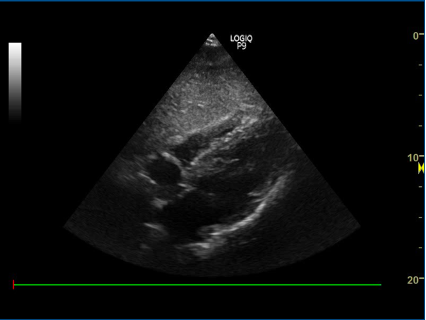

2) Subcostalt billede af IVC:

- Nævn strukturerne:

proben skal pege kranielt